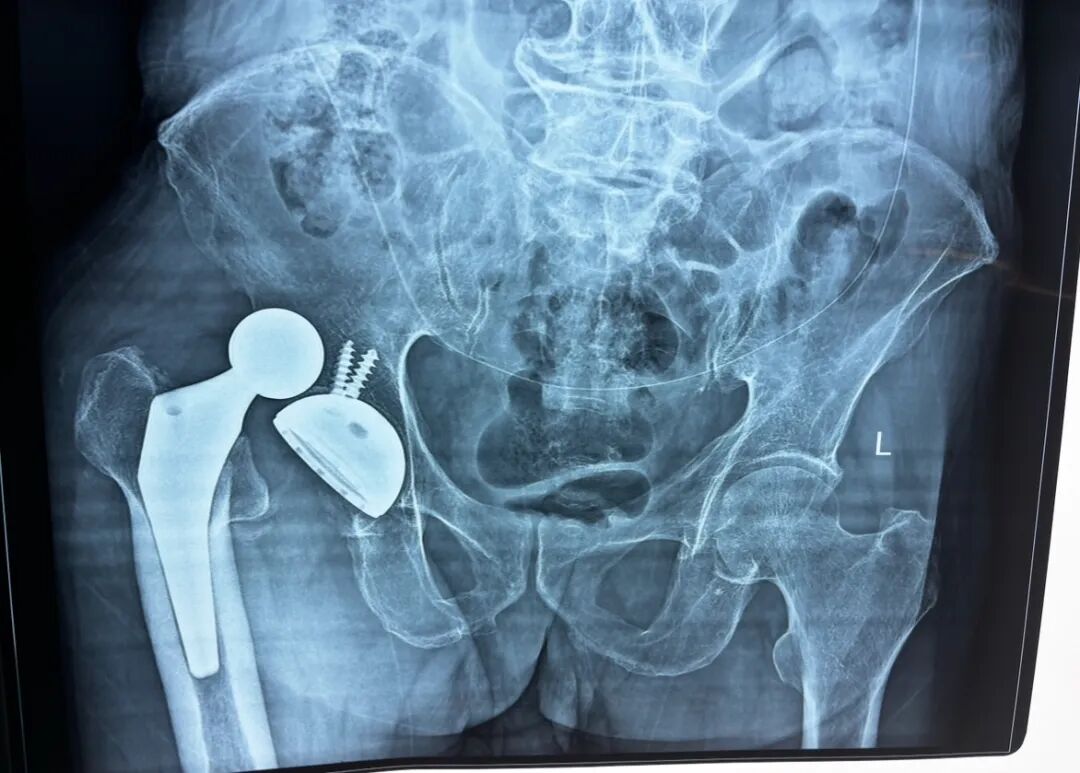

(病例拍摄已经过患者及家属知情同意)

复位成功后应立即行X线摄片和CT 扫描,评估复位情况和是否合并股骨头、髋臼的 骨折,如果髋臼和股骨头的同心结构未能恢复,髋关节仍处于半脱位,提示股骨头或髋臼骨折,需进一步手术治疗,重建髋关节的稳定性。